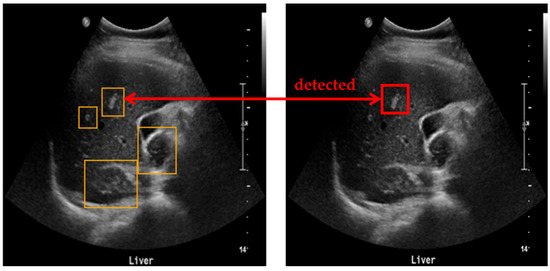

The liver US images used in this study were acquired using the Siemens ACUSON Sequoia 512 system (Siemens Healthineers, Erlangen, Germany), which operates at a frequency range of 3 to6 MHz, with 256 gray levels and a maximum depth of 36 cm. These images were collected under data use agreements and approved by the Institutional Review Board (IRB) of SMC, one of South Korea’s leading hospitals (SMC-2020-10-178-002). The dataset was annotated with two categories: benign and malignant. Since accurate diagnosis using only US images is challenging, the final labels were determined by SMC’s expert physicians after completing all necessary diagnostic procedures, including CT, MRI, and biopsy. The annotation for each patient’s US images was based on these comprehensive findings. Given the goal of our study to develop a screening tool, lesions were categorized simply into benign or malignant, rather than employing more granular labeling. Figure 1 provides examples of benign and malignant cases from our dataset.

Figure 1. Example of US images from dataset. (a) Benign, (b) Malignant.